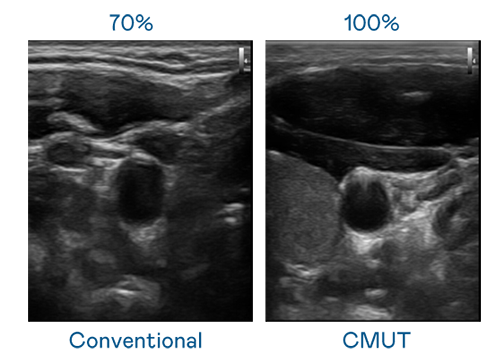

CMUT 技术是一种用电容式微机电元件来产生超音波讯号的技术。与传统 PZT 压电式技术相比,CMUT 频宽增加 30%,更宽频的超音波讯号让影像解析度大幅提升,是实现高影像品质医疗超音波扫描、促进精准医疗发展的关键技术。

超音波影像的解析度高低,首先取决于探头能发出的讯号频宽。创世大发 CMUT 可提供高清晰的超音波讯号,提供高频宽、高灵敏度、影像纹理细节更高的超音波影像,协助医护人员缩短影像判读时间及利用精准的医疗影像进行诊断。